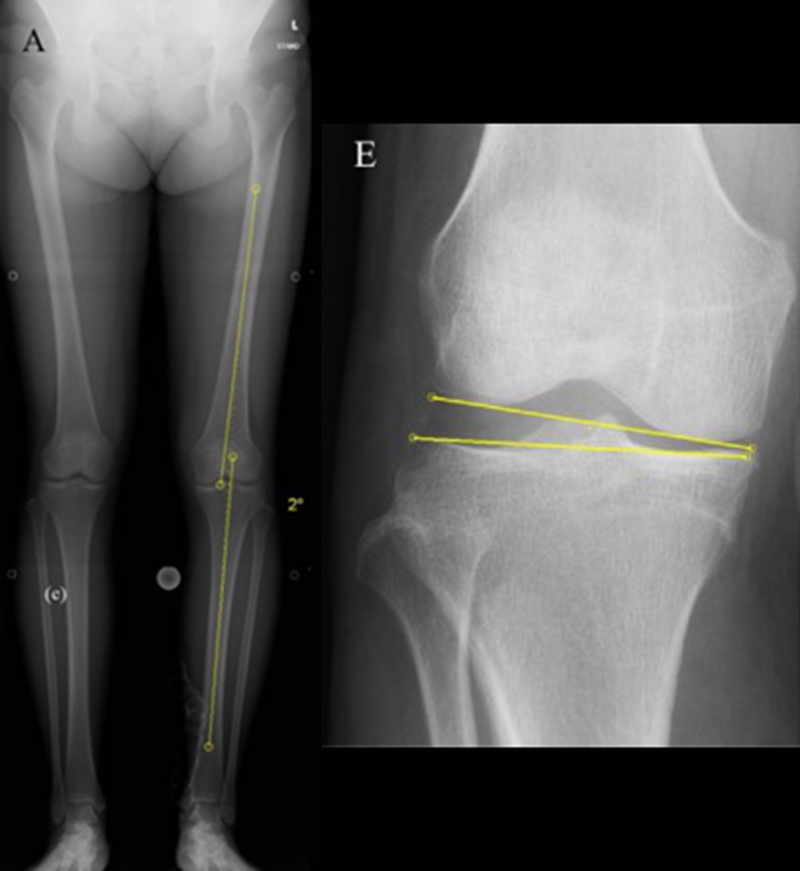

关于SONK与下肢力线的关系,一项研究结果显示SONK组MPTA畸形比OA组更大,高达约1.5°,SONK组JLCA也显著高于OA组。

提示胫骨近端内翻畸形和膝关节松弛,有助于诱发SONK,SONK骨软骨病变的大小受胫骨近端内翻畸形的影响。临床中MPTA小于 84°且伴有急性膝关节疼痛应尽快MRI检查。

病例1:男,64岁,主诉左膝关节内侧疼痛6年余。MR提示骨坏死区占比为33.28%,矢状位病变区域前后径为26.42mm,半月板相对突出百分比(RPE)31.78%,同时存在胫骨侧来源的下肢内翻畸形(MPTA83°),关节线会聚角2°。